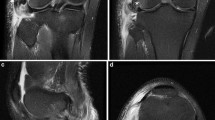

The current gold standard for PLC and PFL imaging evaluation is magnetic resonance imaging (MRI) [18], performed most successfully via T2-weighted coronal and oblique coronal scans [1, 5]. However, MRI detection is complicated by several factors, including the PFL’s location in the deepest layer of the PLC, morphological variations, and, most importantly, the possibility that the PFL will not be visible on scans due to the partial volume effect [1, 5, 6, 19, 20].

The PFL is considered a constant structure within the human knee. However, its prevalence is lower among MRI studies than in cadaveric investigations [20]. This is most likely due to gaps between established MRI examination cross-sectional slices (partial volume effect) that miss the thin PFL; as a result, the PFL (a sheet-like structure) may be excluded from MRI cross-sections, making its assessment difficult through this modality [1, 5, 6, 20]. As injury to the PFL may lead to severe morbidity and is a cause of failure of ACL reconstruction surgery, it is important to fully assess this structure in the case of complex knee injuries [17]. Ultrasound, due to its ability to obtain variable cross-sections in real-time, can be considered a useful diagnostic tool for orthopedic surgeons assessing and treating knee trauma [11, 25].